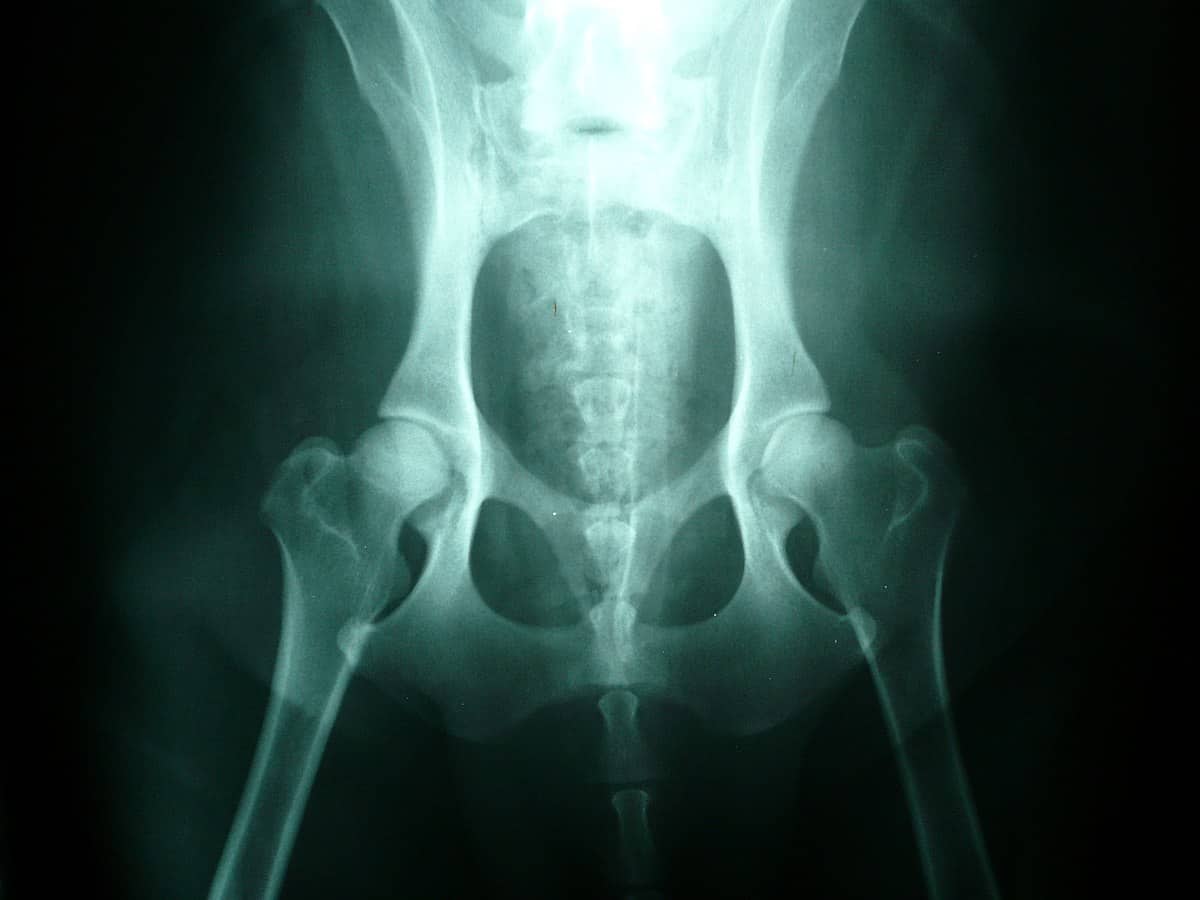

Can Hip Dysplasia Cause Knee Pain In Dogs . your dog’s lifestyle can affect the degree of pain. Working dogs may exhibit more pain than less active house pets. if you suspect your dog has hip dysplasia, see your veterinarian for proper diagnosis. hip dysplasia is a common inherited disease in dogs. This causes unusual wear and tear on. but when a dog suffers from hip dysplasia, the ball and socket elements that make up their hip joint rub and grind unpleasantly. It can be very painful and can cause other conditions, such as arthritis. dysplasia (meaning ‘abnormality of development’) is when a dog’s hip joint grows abnormally. Germai what is hip dysplasia in dogs? hip dysplasia in dogs is a developmental disorder caused by a loose hip joint, which can be painful for your dog.